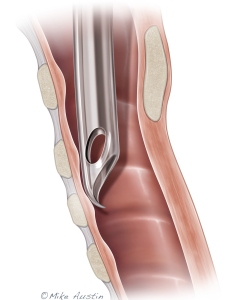

Welcome to my Patient and Professional Marketing page, where I harness the power of anatomical illustrations to educate and empower both patients and medical professionals. My unique approach combines artistry and education to convey complex surgical procedures and the utilization of medical devices in an easily understandable manner.